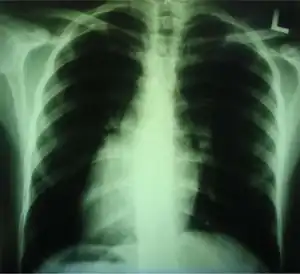

Dextrocardia (from Latin dextro, meaning "right hand side," and Greek kardia, meaning "heart") is a rare congenital condition in which the apex of the heart is located on the right side of the body, rather than the more typical placement towards the left.[1][2]

Medical diagnosis of the two forms of congenital dextrocardia can be made by ECG[3] or imaging.